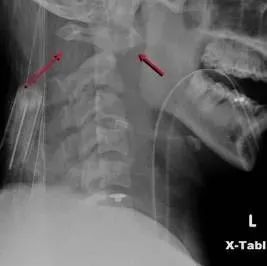

一、 寰枢关节脱位

常见于过伸位损伤,如向前滑倒;儿童多见于成人;通常有生命危险。

二、寰椎后弓骨折

是C1常见的骨折,常由于过伸位损伤造成,不伴有神经损伤,可伴有先天畸形。